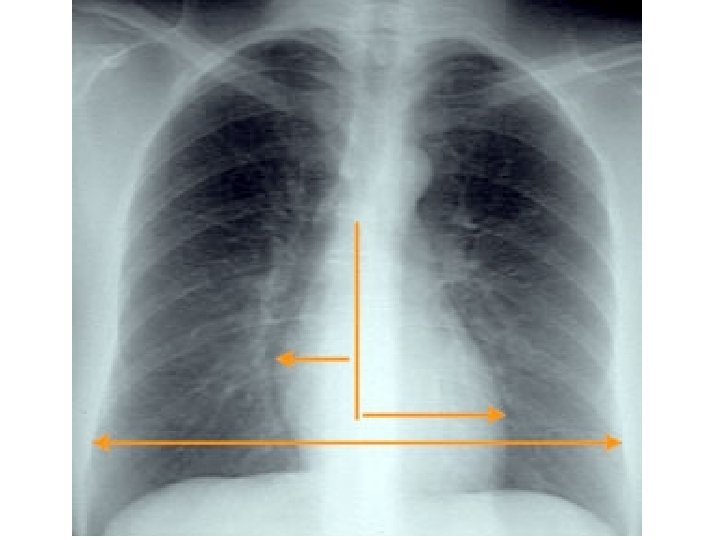

Dark lungs AP diameter Low flat diaphragms Vertical heart Retrosternal air Infracardiac air Avascularity

Dark lungs AP diameter Low flat diaphragms Vertical heart Retrosternal air Infracardiac air Avascularity Blebs Emphysema